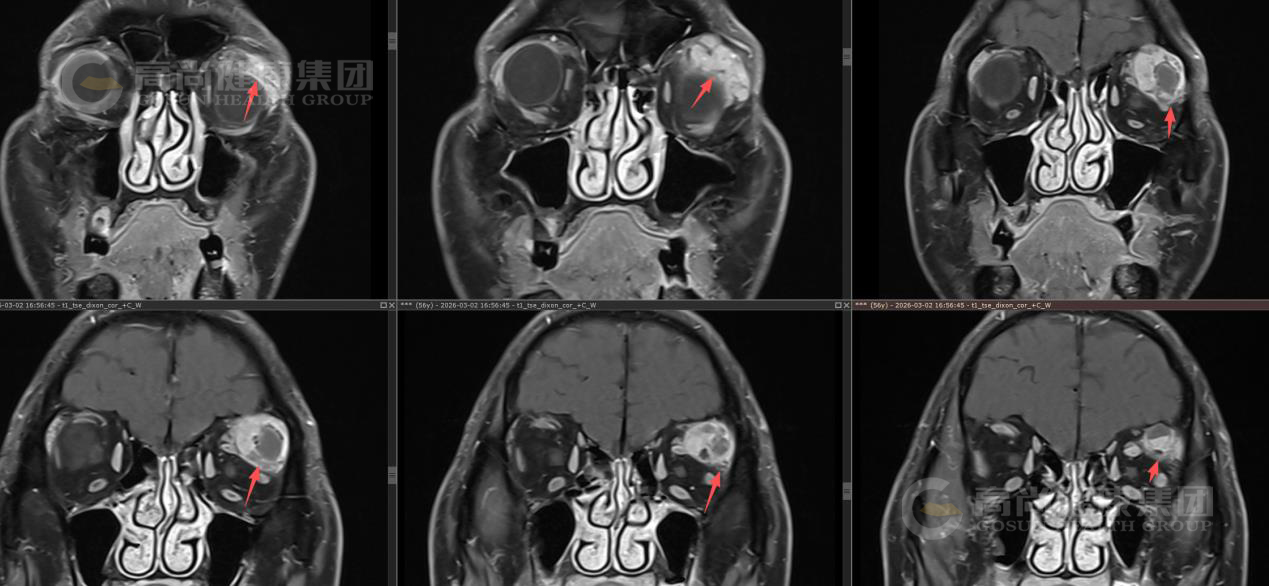

眼眶MR平扫+增强扫描

序列 T1WI T2WI T2WI-FS DWI/ADC T1-VIBE+C 3D-T1WI+C

方位 TRA SAG COR

左眼眶外上泪腺区类圆形异常信号影,大小约23×26×26mm(左右径×前后径×上下径),呈囊实性改,T1WI呈等信号,T2WI及T2WI-FS序列主要呈稍高信号伴囊样高信号,实性部分DWI呈轻度高信号,囊性部分呈等信号,ADC实质部分呈低信号,囊性部分呈高信号。

MR增强扫描: 肿块实质部分呈明显强化,且持续强化,囊变区不强化,病灶累及左眼眶肌锥内外间隙,与邻近泪腺界限不清,左侧眼球受压、向前突出,左侧上直肌、外直肌轻度受压。

影像诊断结果: 左侧泪腺区肿瘤性病变,考虑泪腺混合瘤,部分囊变坏死,不除外其它,请结合临床。